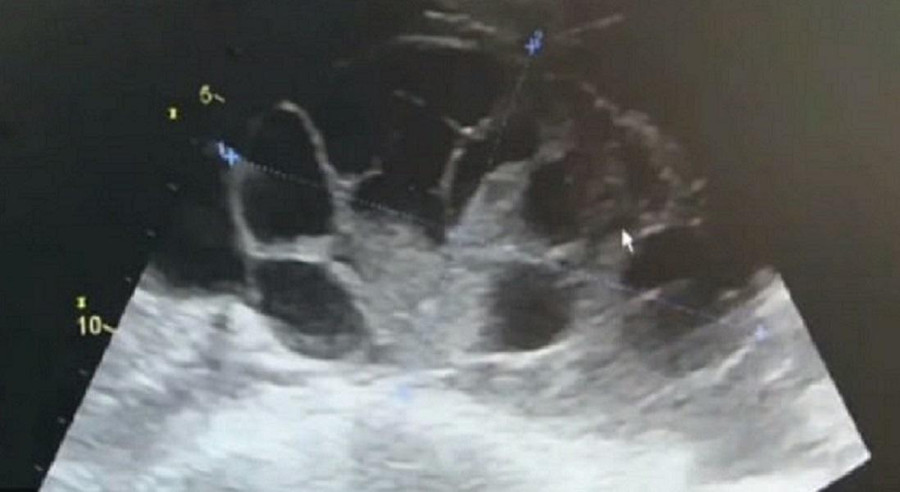

Ba ngày sau cuộc phẫu thuật bất hợp pháp, cô đổ bệnh và phải nhờ đến sự giúp đỡ của các bác sĩ tại bệnh viện trường Đại học Y khoa Chiết Giang. Cô được chẩn đoán là mắc hội chứng quá kích buồng trứng, điều này có thể xảy ra khi cố kích thích sự phát triển của trứng và chất lỏng tích tụ xung quanh.

Bác sĩ Hu Jinhui của khoa phụ sản ở bệnh viện cho biết: “Buồng trứng của cô ấy bị mở rộng như thể đã mang thai được bảy hoặc tám tháng. Bệnh nhân sẽ phải chịu đau đớn, khó thở và có thể đe dọa đến tính mạng”.

Kết quả chẩn đoán cô đã bị mắc chứng quá kích buồng trứng.